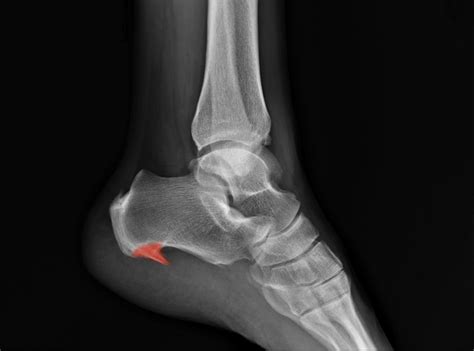

• Bone Spurs: These are bony projections that can form on the heel bone due to chronic stress or inflammation. Bone spurs can cause pain and discomfort, especially during weight-bearing activities.

• Arthritis: X-rays can also reveal signs of arthritis, such as joint space narrowing and bone spurs, which can affect the heel and surrounding joints.

• Heel Spurs: These are bony projections that can form on the underside of the heel bone. They are often associated with plantar fasciitis and can cause significant pain and discomfort.

• Plantar Fasciitis: This condition involves inflammation of the plantar fascia, a thick band of tissue that runs along the bottom of the foot. While not directly visible on an X-ray, a Calcaneus X Ray can help rule out other causes of heel pain.

Each of these conditions requires a different approach to treatment, and a Calcaneus X Ray plays a crucial role in guiding the appropriate course of action.